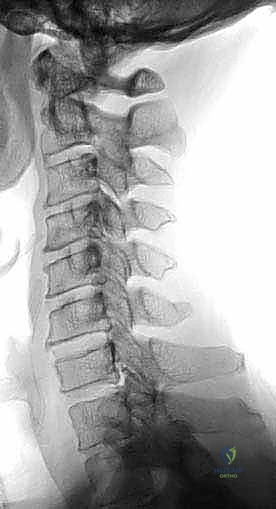

- التصوير بالرنين المغناطيسي (MRI): المعيار الذهبي لرؤية الحبل الشوكي، الأعصاب، والأقراص الغضروفية بوضوح تام، وتحديد مناطق الانضغاط.

- التصوير المقطعي المحوسب (CT Scan): ضروري جداً لتقييم البنية العظمية، التكلسات (مثل OPLL)، والكسور بدقة ثلاثية الأبعاد.

- الأشعة السينية الديناميكية (X-Rays): لتقييم استقرار العمود الفقري أثناء ثني ومد الرقبة.